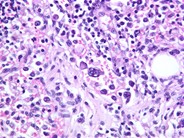

Intravascular Large Cell Lymphoma - 2.

Category: Lymphoma: Mature B-cell and Plasma cell Neoplasms > Large B-cell lymphomas (not Richter transformation) > Intravascular large B-cell lymphoma

The lymphoma cells are large with irregular nuclear contours, clumped chromatin, and prominent nucleoli. These cells were immunoreactive for pan B-cell markers CD20 and CD79a.